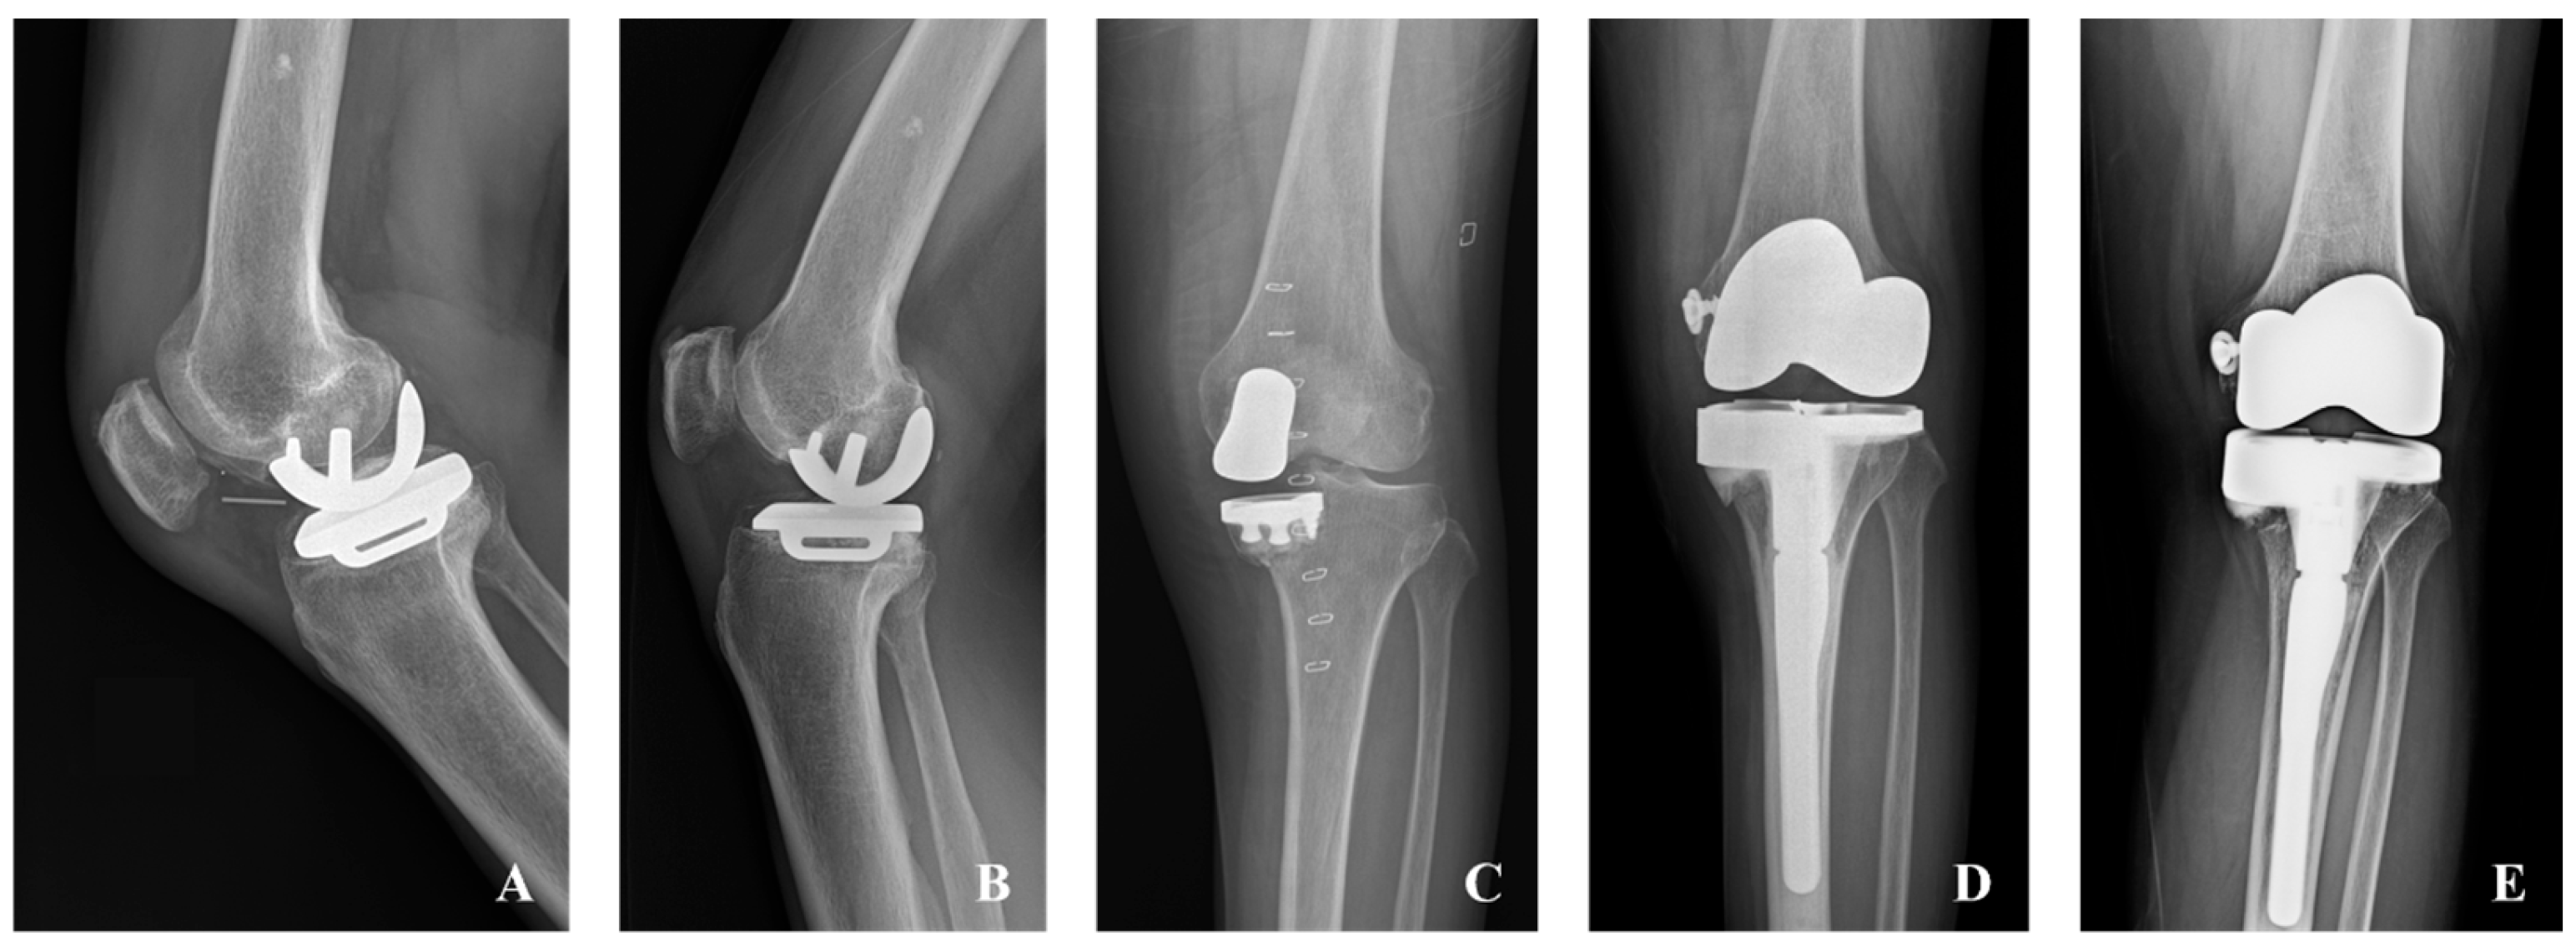

2.2. Surgical Treatment

| Failure (TKA conversion) | 7 (8.6%) | 1 (2.2%) | 6 (16.7%) | 0.041 |

| Failure (TKA conversion or PE exchange) | 9 (11.1%) | 1 (2.2%) | 8 (22.2%) | 0.009 |